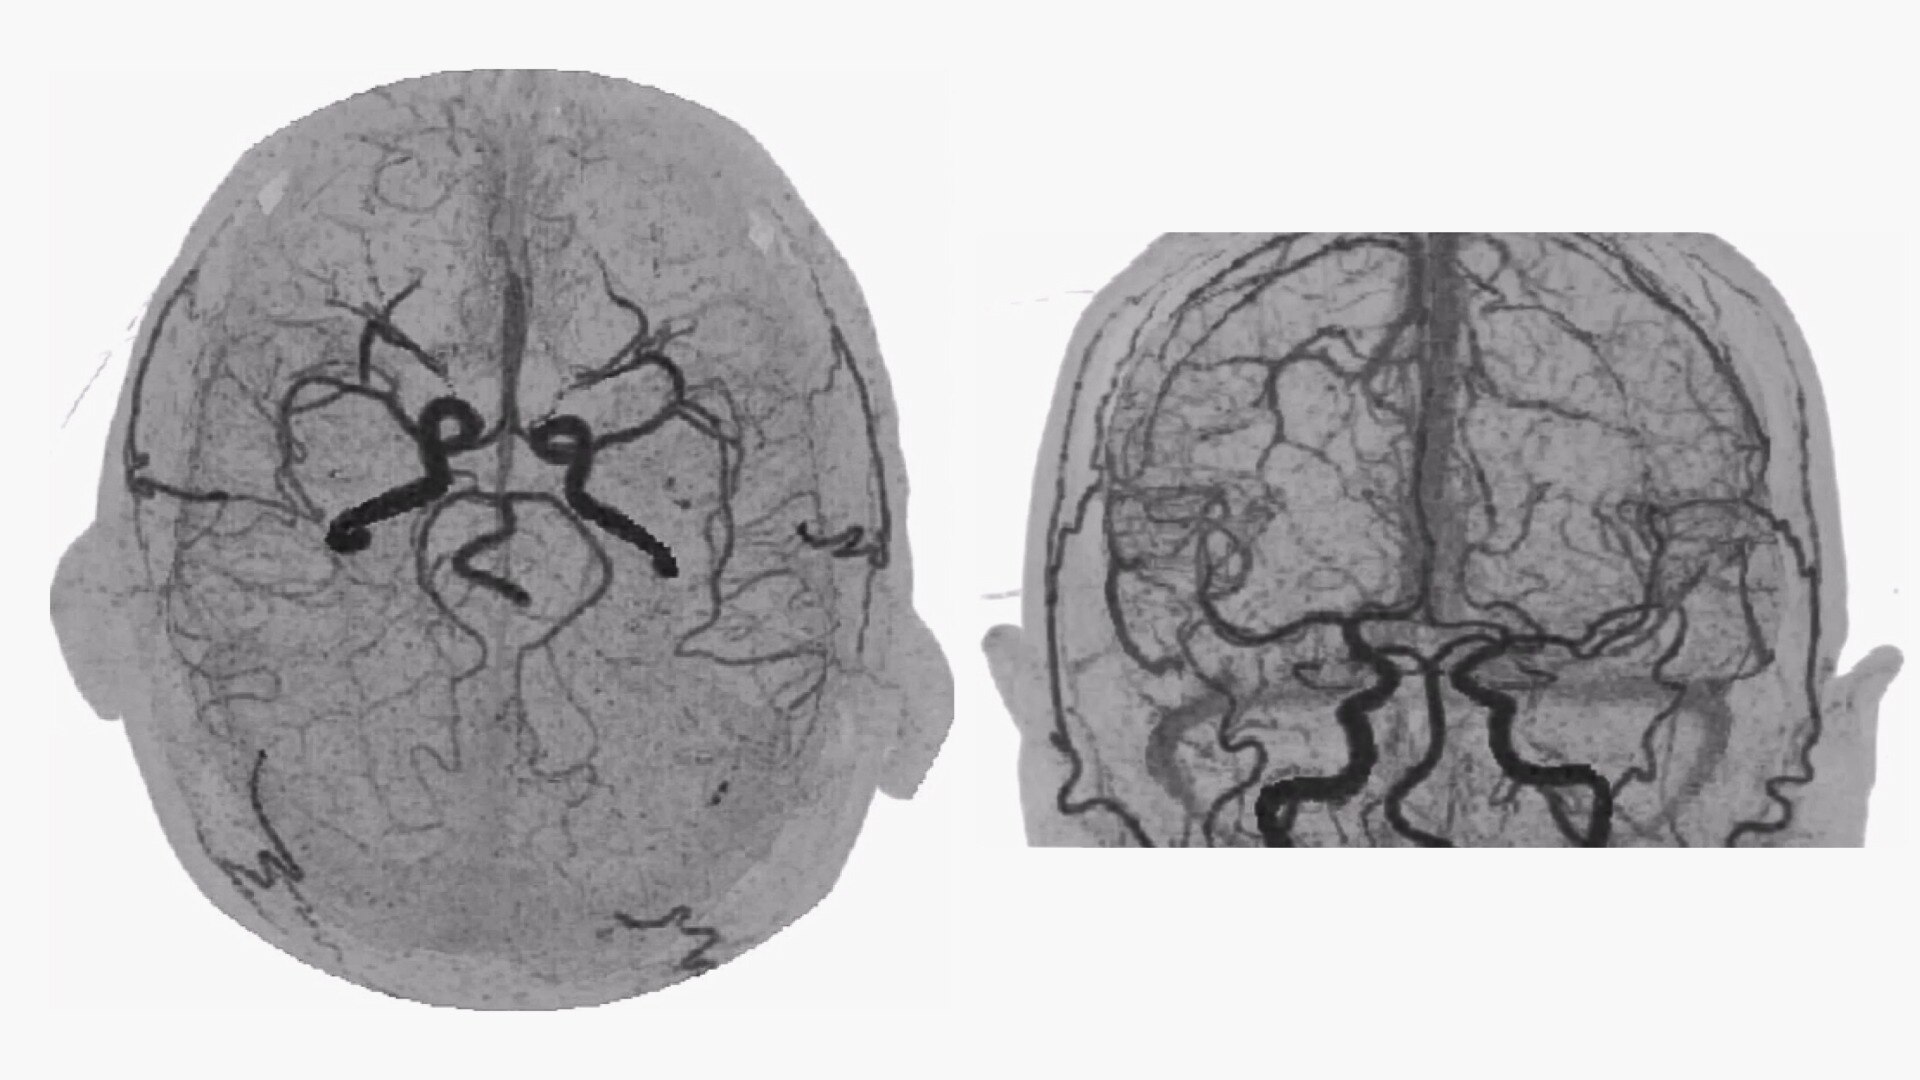

Bone-free dynamic visualization of vascular anatomy.

Allows vascular diagnoses using dynamic CT angiography.

Extracts data from scan and visualizes the flow of contrast from the arteries to the veins.

• 4D Neuro Digital Subtraction angiography (DSA) automatically performs image registration, then removes bone.

• 4D Body Shuttle loads dynamic data into the body protocol after which you can apply either Bone Subtraction DSA or Autobone Shuttle. The program then registers the image and removes bone using the selected protocol.